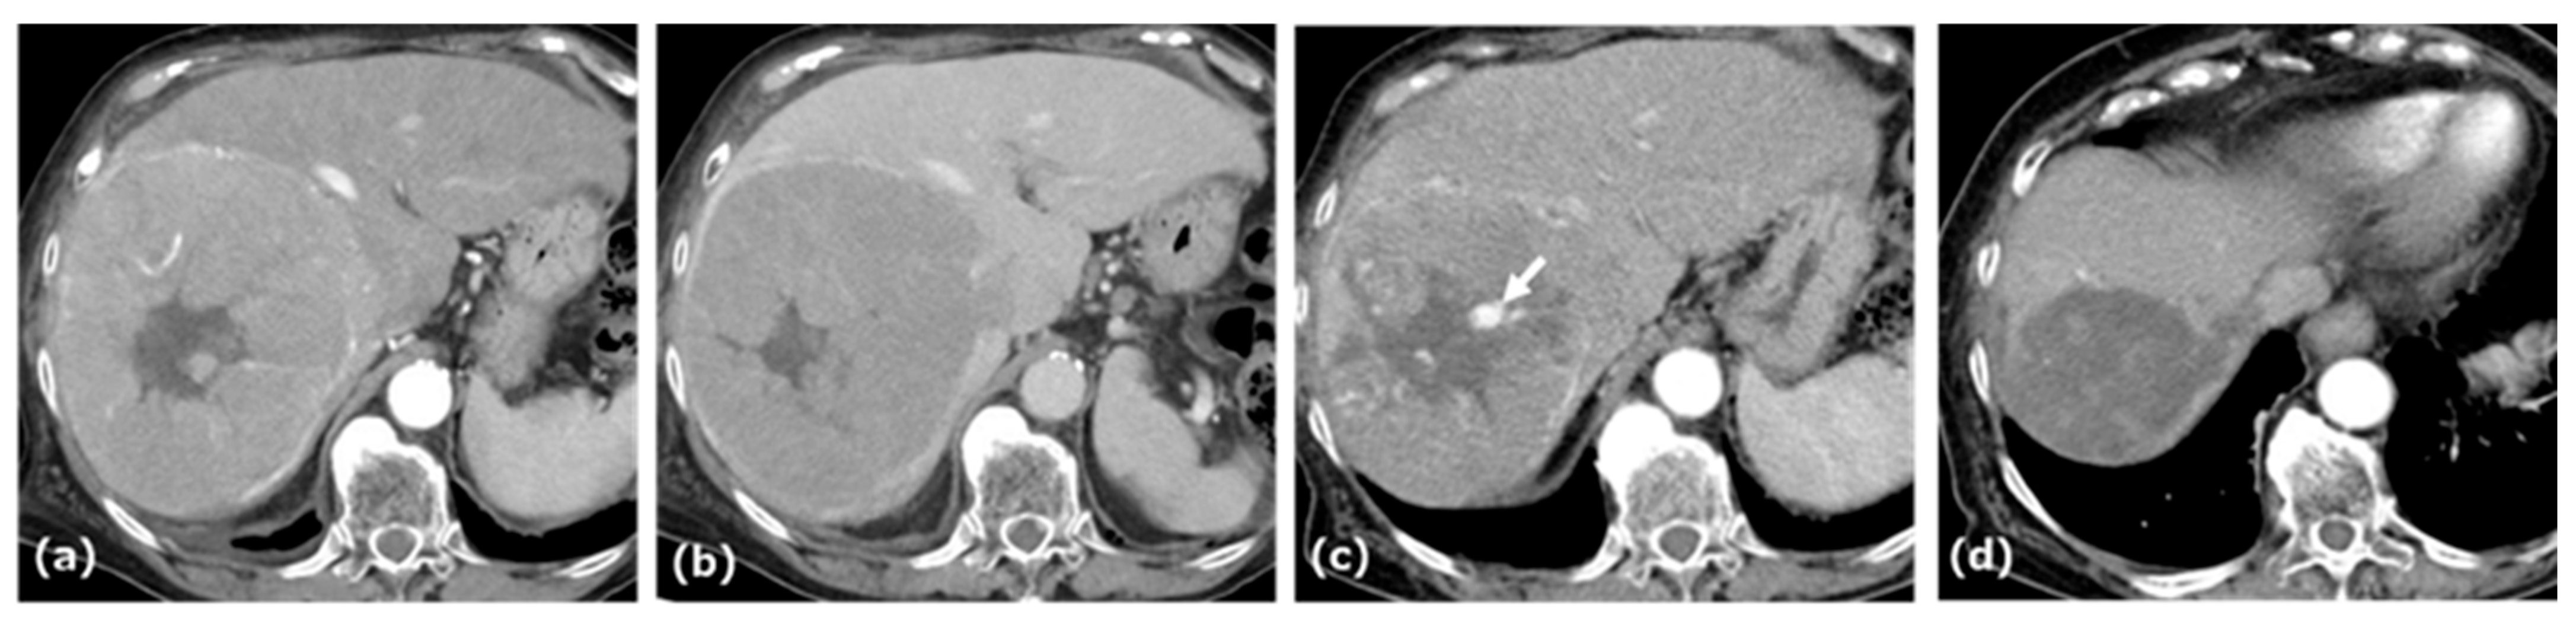

2.2. Case 2